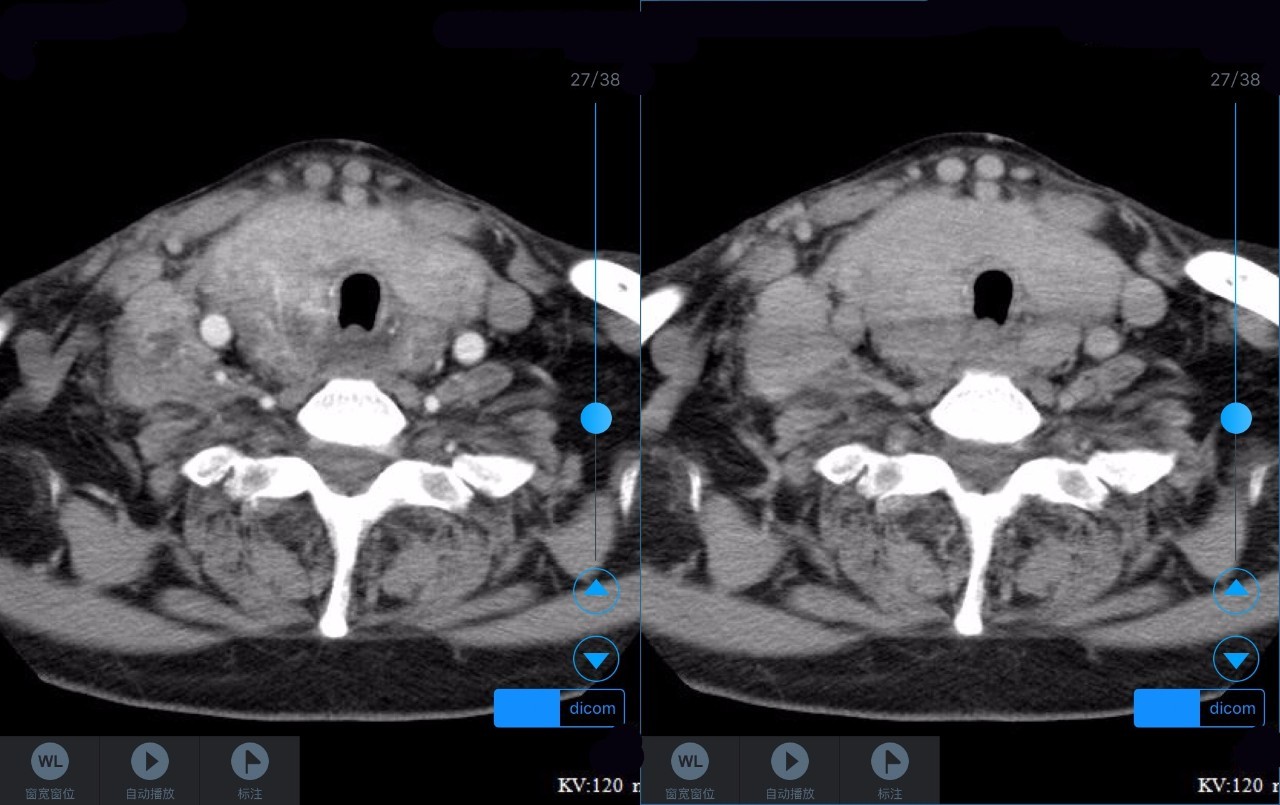

▼患者CT平扫(右)及增强CT(左)检查报告资料

Z主任 甲状腺肿大,内见弥漫多发结节,界限不清,甲状腺包膜毛糙。双侧颈部、锁骨上、纵隔多发肿大淋巴结,病变均强化明显,密度不均,边缘毛糙,考虑甲状腺恶性肿瘤伴多发淋巴结转移,或甲状腺内也是转移瘤。Castleman病多灶者少见,一般病变边缘光整,也不会累及甲状腺。建议穿刺活检。 C主任 双侧甲状腺肿大,密度不均,不均匀强化,甲状软骨未见明显骨质破坏气管右侧壁受压;双侧颈部多发肿大淋巴结,不均匀强化;考虑为甲状腺恶性占位性病变伴双侧颈部淋巴结转移,建议组织学进一步检查。 声明:以上资料均来自和缓名医平台的真实案例,为保护用户隐私,均用化名代替。资深医师Z咨询反馈